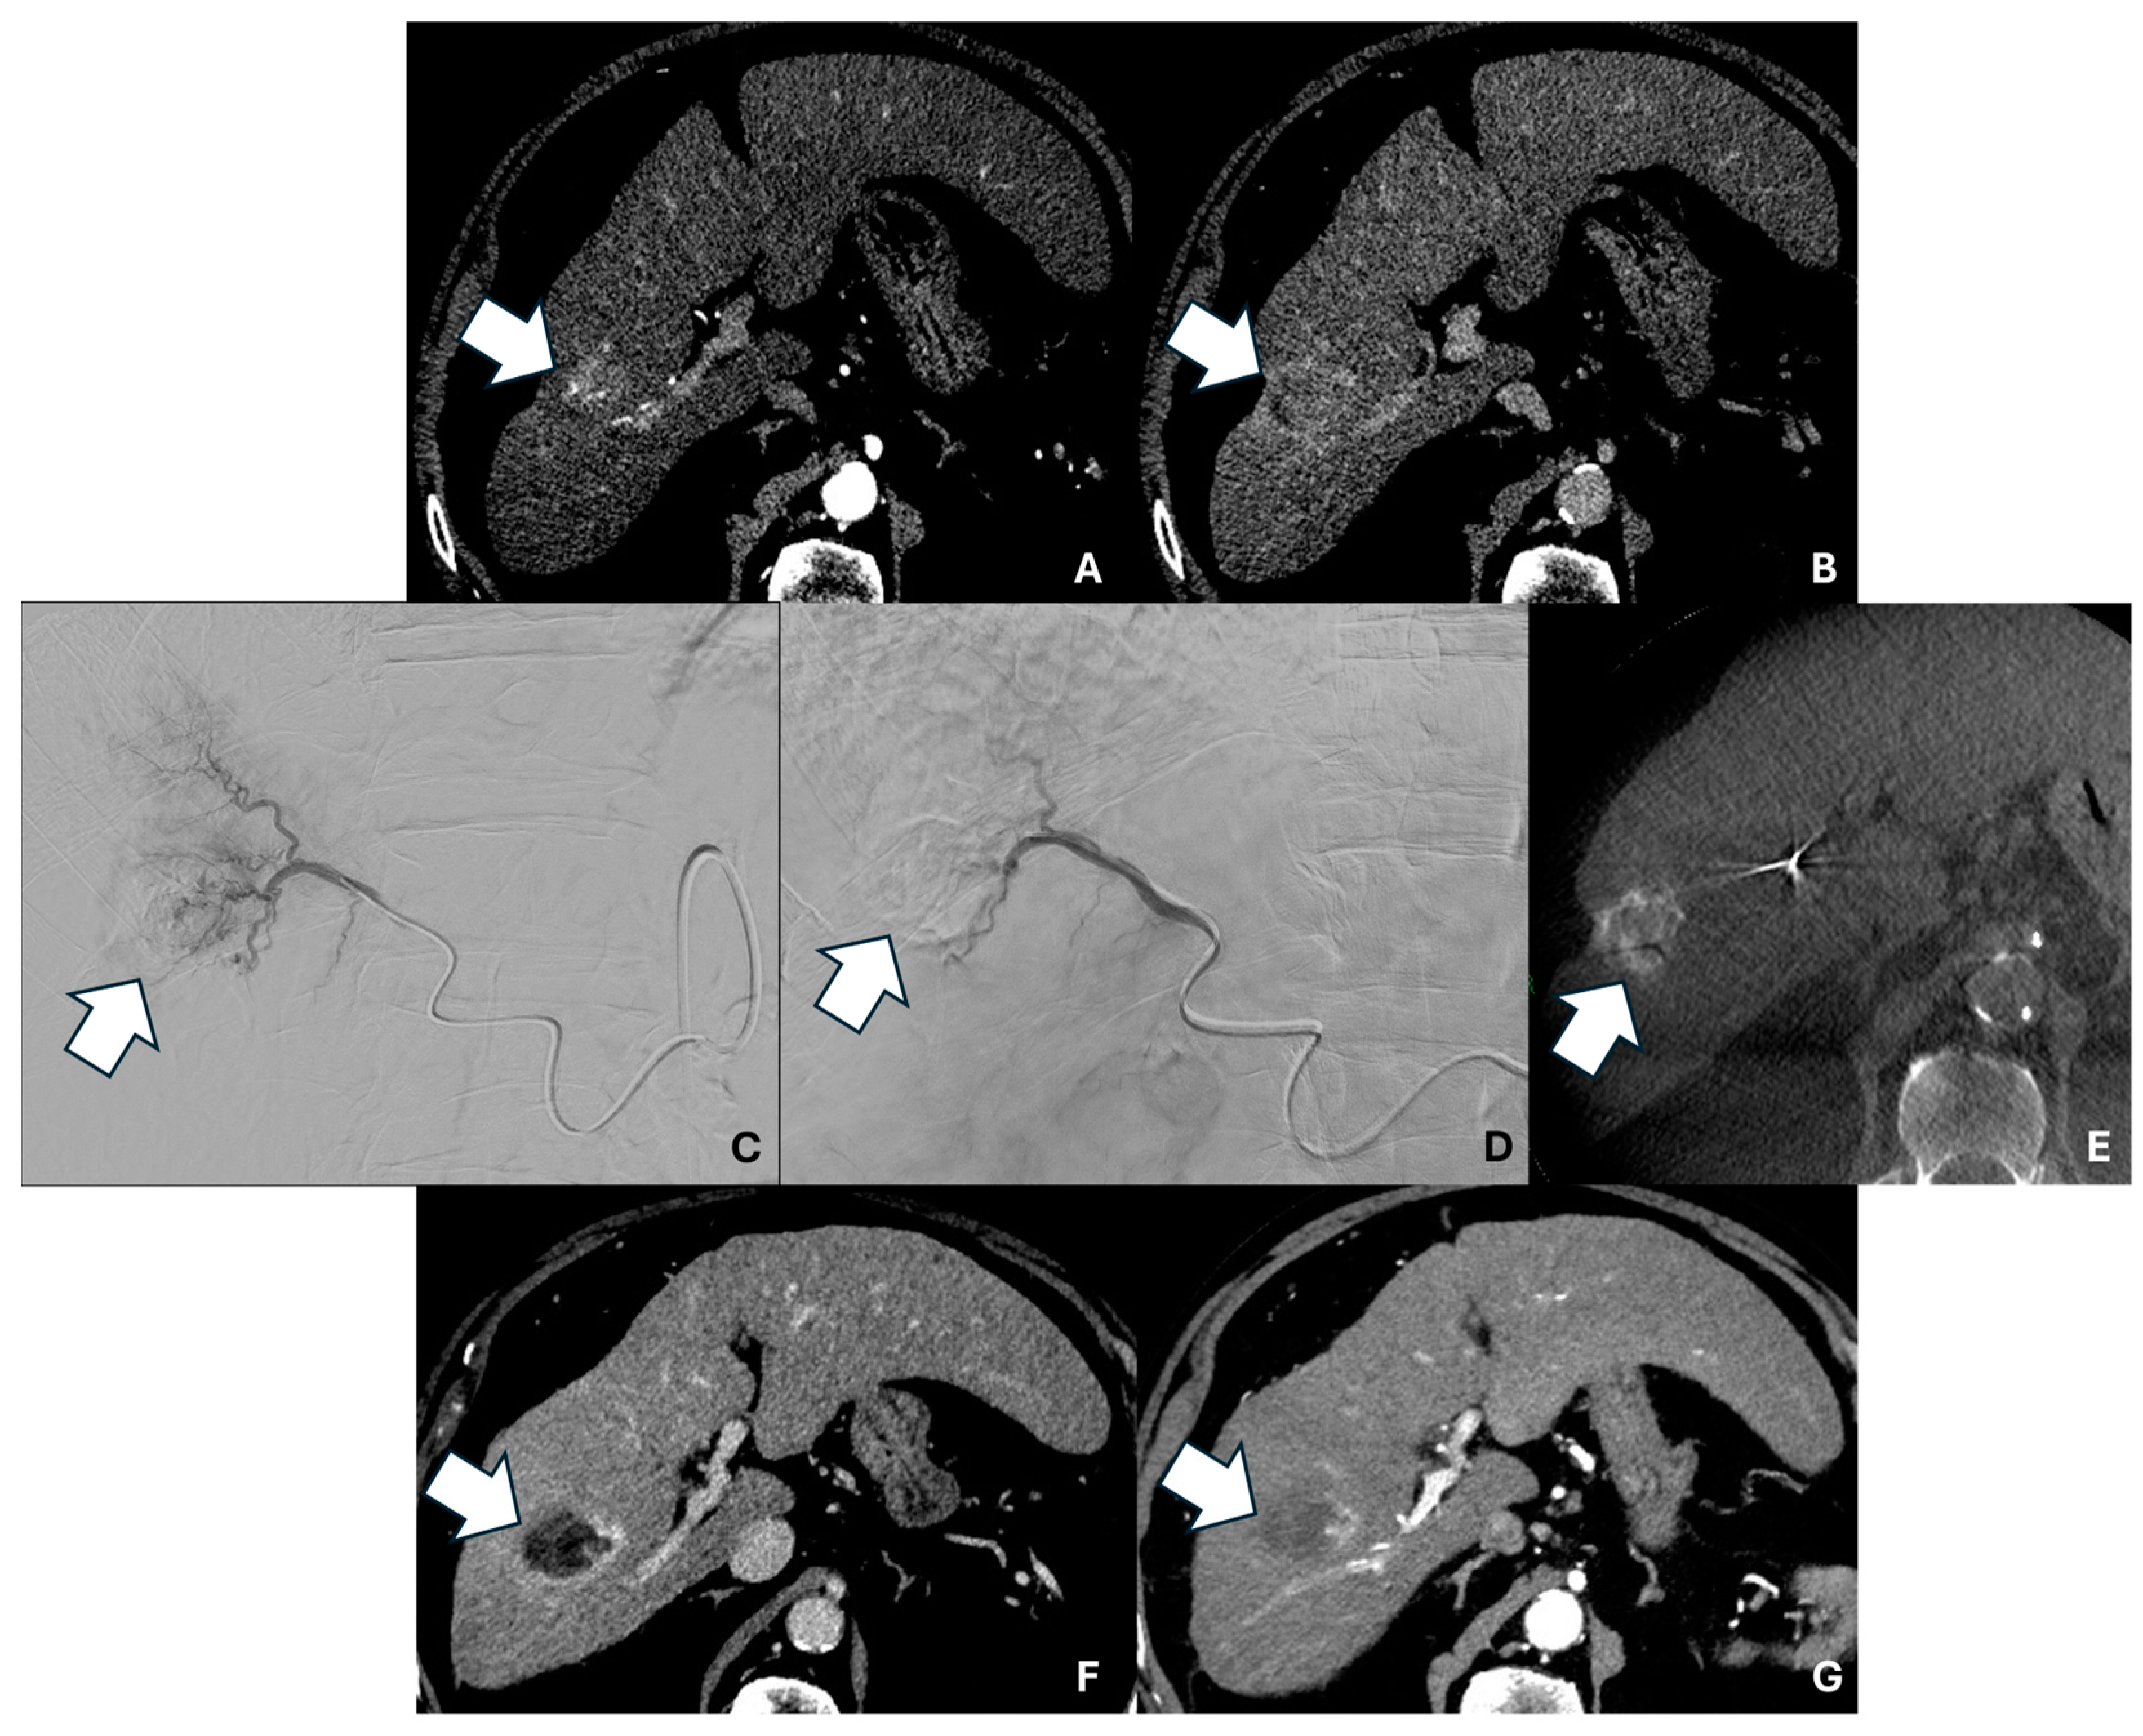

Figure 1 shows the pre-, intra-, and post-procedural imaging of a patient with CR.

Figure 1. Axial contrast-enhanced pre-procedural CT scan in the arterial (A) and delayed (B) phases showing a 27 mm HCC nodule in the VII segment (arrows). (C) Digital subtraction angiography (DSA) image showing superselective microcatheterization of the HCC lesion with pre-TACE tumor staining. (D) Post-TACE superselective DSA image. (E) Post-TACE unenhanced cone-beam CT acquisition showing iodinated contrast medium and microsphere uptake by the lesion, with complete coverage (arrow). Axial contrast-enhanced 1 month post-TACE CT scan in the arterial (F) and delayed (G) phases showing complete response (arrows).